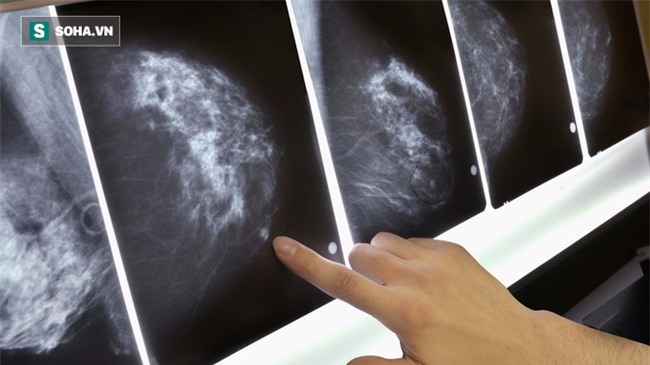

Độ dày đặc của mô vú không thể cảm nhận hoặc quan sát bằng mắt. Các bác sĩ sử dụng phương pháp chụp quang tuyến vú (mammogram) để quan sát mô vú. Nữ giới ở độ tuổi trẻ thường có nhiều mô bào đặc ở vú.

Khi quan sát bản đồ quang tuyến vú, mô mỡ ở vú có màu tối còn mô bào đặc có màu trắng

Khi quan sát bản đồ quang tuyến vú, mô mỡ ở vú có màu tối còn mô bào đặc có màu trắng. Việc phân biệt với mô bào đặc và khối u ở vú rất khó vì các khối u trên bản đồ quang tuyến vú cũng có màu trắng.